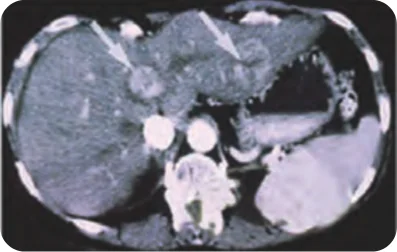

Alcohol Injection Therapy, also known as Percutaneous Ethanol Injection (PEI), is a minimally invasive treatment that uses concentrated alcohol to destroy tumor tissues. Guided by ultrasound or CT imaging, a puncture needle is carefully advanced through the skin into the tumor’s interior, where 100% alcohol is slowly infused. The alcohol causes cellular dehydration and protein denaturation, leading to tumor necrosis and shrinkage.

Typically, 5–6 doses of alcohol injection are sufficient to effectively treat the targeted tumor area. The procedure is performed under imaging guidance to ensure precise delivery, minimizing damage to surrounding healthy tissues.